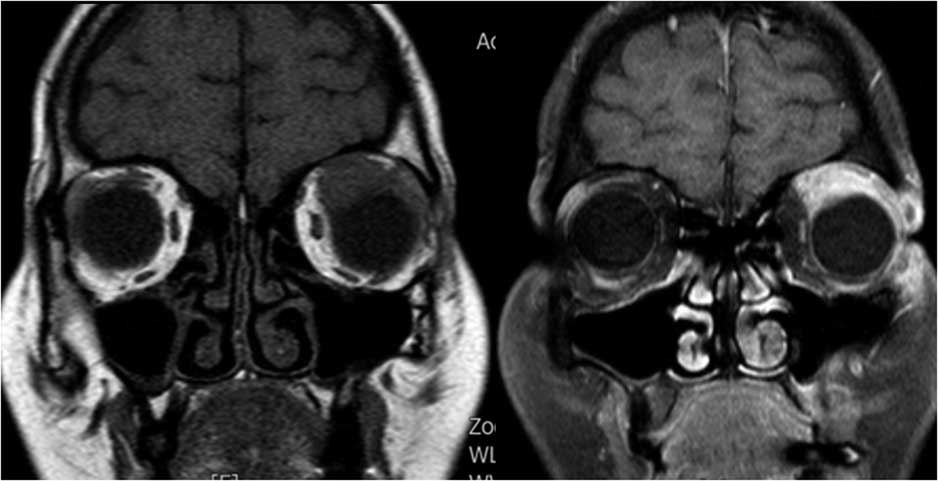

Case 1: A 42-year-old female presented with a 2-week history of left-eye ptosis and a moderate orbital pain. Clinical examination showed a marked ptosis on the left eye (Figure 1a). Visual acuity was normal, and there was no other ocular movement abnormality except for slightly limited elevation of the left side. Levator excursion was mildly reduced on the left side compared to the right. Laboratory tests revealed only a slightly elevated C-reactive protein (CRP) and sedimentation rate, but other investigations, including complete blood count (CBC), thyroid function test (TFT), antithyroid antibodies, anti-nuclear antibody (ANA), anti-neutrophil cytoplasmic autoantibody (ANCA), viral serology, IgG4 levels, and anti-acetylcholine receptor (AChR) antibodies were all normal. Orbital magnetic resonance imaging (MRI) showed enlargement and contrast enhancement of the left superior rectus and left levator palpebrae superioris (Figure 1b). Cerebrospinal fluid (CSF) examination was unrevealing. Brain MRI, intracranial MR angiography, and chest CT revealed no abnormalities. Treatment with intravenous methylprednisolone (1 g/day for 3 days) was initiated and followed by oral prednisolone (1 mg/kg/day). Symptoms gradually resolved, and a clear improvement occurred over the following 3 weeks (Figure 1c). Repeated MRI scan performed 2 months after the first MRI revealed marked improvement of the levator palpebrae swelling (Figure 1d). Steroids were slowly reduced and stopped over the following 3 months. The patient remained symptom-free at follow-up.

Figure 1b Coronal MRI scan of orbits shows enlargement and contrast enhancement of the left superior rectus and left levator palpebrae superioris.

Figure 1d Repeat MRI after 2 months revealed marked improvement of the levator palpebrae swelling.